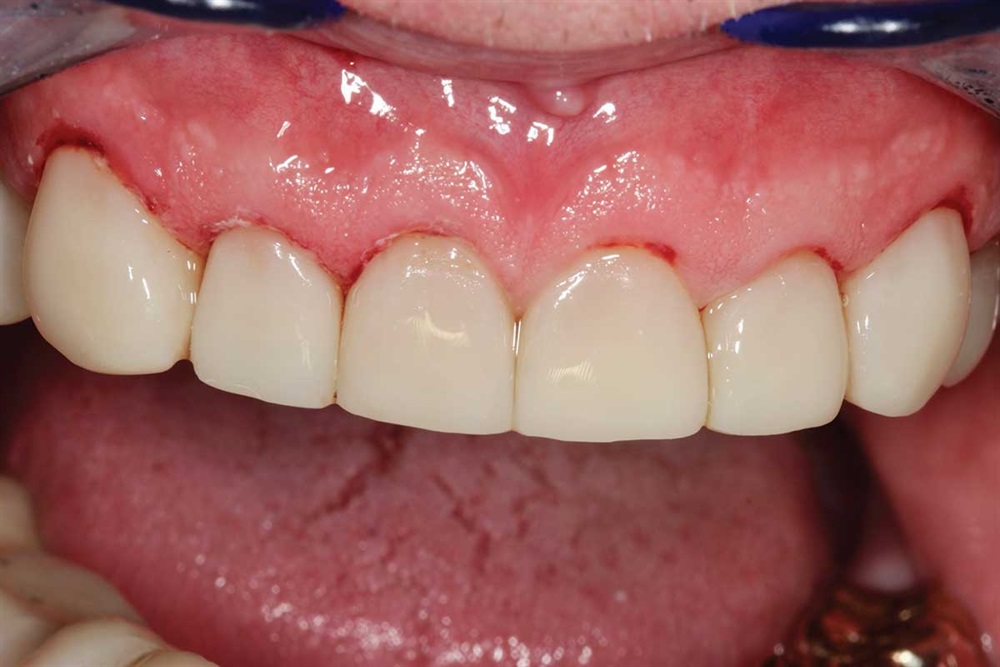

Procedure 2: Top teeth

Show Your Work

Fig. 21: September 2018. First picture from his second go-round. Not brushing the lowers well.